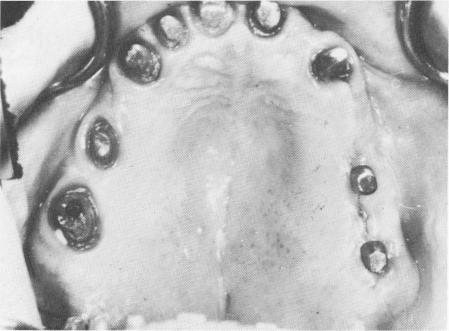

side of the mandible between the cuspid and the wisdom tooth (Fig. 11-62), and the site was closed with simple surgical ties (Fig. 11-63) .